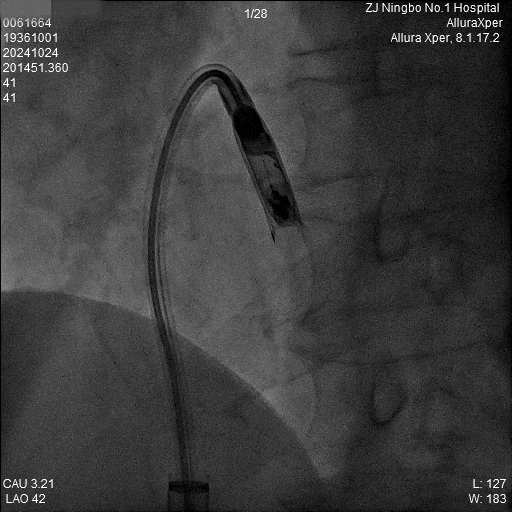

3.调弯进入右室低位间隔后造影,位置理想。左前造影明确贴靠间隔。

a)RAO